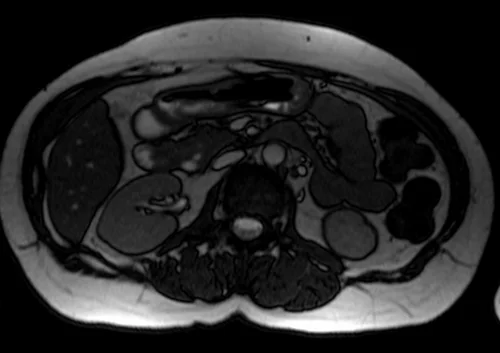

mrcp axial trufi image 1 - MRI